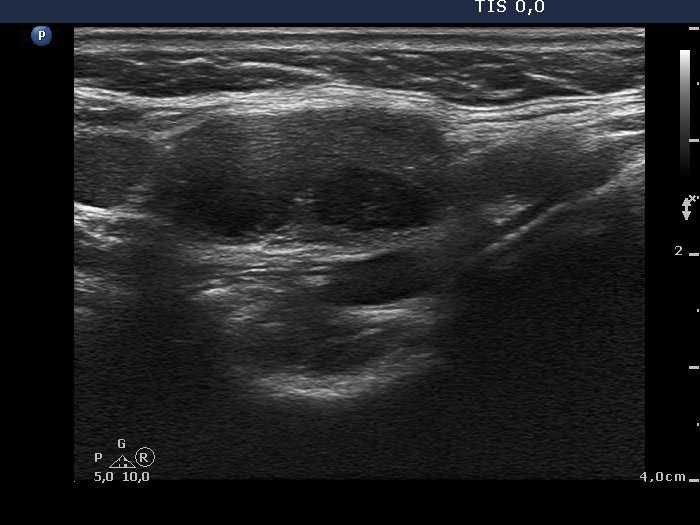

Ultrasonography. The right thyroid was moderately hypoechogenic without any circumscribed lesions. The left thyroid was removed. There were several enlarged lymph nodes in the right submandibular area. The largest one presented two discrete, more hypoechogenic intranodal lesions and a regular hilum.

Comment. This is an unusual case, the nodes (particularly those presented in the video) seem to be benign, reactive-type ones.